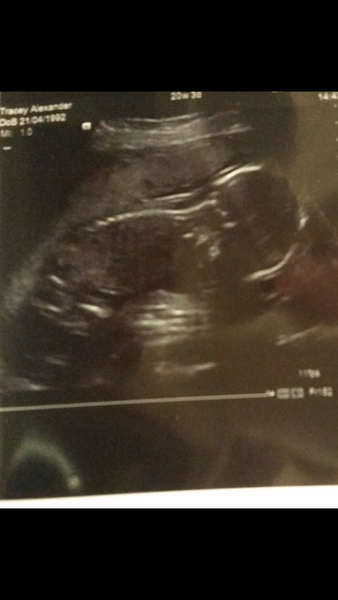

traceybaybee · 26/01/2015 20:37

Popping in to say hello. And to ask with regards to anterior placentas when roughly movement will be felt? Ive had fluttery niggles but cant say for definete its baby moving. Here wee one from my scan on friday